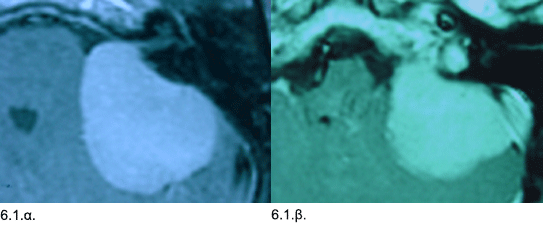

Εικόνες 6.1.α. & 6.1.β. Η μαγνητική τομογραφία δείχνει την μάζα του όγκου στο επίπεδο των ανώτερων κρανιακών νεύρων με τμήμα του όγκου να επεκτείνεται εντός του έσω ακουστικού πόρου (6.1.α.) και σε εγκάρσια τομή στο επίπεδο των κατώτερων ενδοκρανιακών νευρών (6.1.β.).

Ιστορικό: Aσθενής 57 ετών, προσήλθε με μείωση ακοής, εμβοές, αστάθεια και γενικευμένη αδυναμία προοδευτικά επιδεινούμενα κατά τα τελευταία δύο χρόνια. Η κλινική εξέταση έδειξε οριζόντιο νυσταγμό. Κατά τον απεικονιστικό έλεγχο διαπιστώθηκε ένας μεγάλος όγκος διαμέτρου 4 εκ. στον οπίσθιο εγκεφαλικό βόθρο αριστερά. Έγινε οπισθοσιγμοειδική κρανιοτομία και ολική αφαίρεση του όγκου, ο οποίος αποδείχθηκε ότι ήταν μηνιγγίωμα. Η μετεγχειρητική πορεία ήταν ομαλή και η ασθενής δεν ανέπτυξε άλλα νευρολογικά προβλήματα.